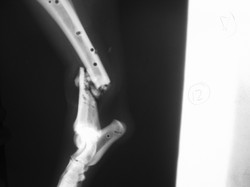

Fijación Externa

PRÁCTICAS CURSO DE FIJACIÓN EXTERNA PERFECCIONAMIENTO.

Híbrido.